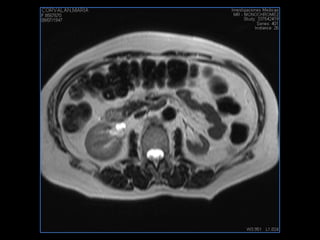

PROTOCOLO abdomen COR T2, AXIAL supresion grasa AX T1 +SAG T2  CON   GADOLINIO :  COR T1+AX T1(DIN) SAT: NO  FASE: RL THK: 6MM  COIL:  GAP: (FACTOR 1.4) 2MM FOV: 40 CM NEX:2 SINCRONIZACION RESPIRATORIA EN 3 O 4 CICLOS ALE

PROTOCOLO pancreas/ riñon AXIAL fat sat /AX in phase out phase AX T1 +SAG T2  COR T2, CON   GADOLINIO :  COR T1+AX T1(DIN) SAT: NO  FASE: RL THK: 4MM  COIL:  GAP: (FACTOR 1.4) 1MM FOV: 40 CM NEX:2 SINCRONIZACION RESPIRATORIA EN 3 O 4 CICLOS ALE